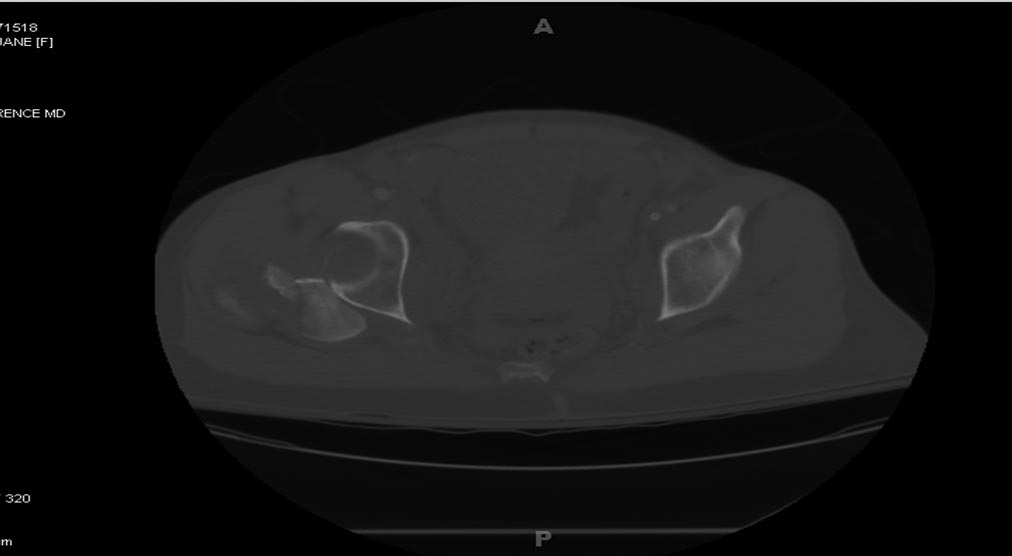

Здесь перечислены ортопедические повреждения: Rt. femoral shaft fracture, Rt femoral head fracture-dislocation, Rt distal femur fracture, Rt. open patella fracture, Rt. talus fracture dislocation, Rt. open humerus fracture, Left 5th metatarsal fracture, Left dislocation 1st TMT.

На 25 день с момента травмы операция на Jackson table с боковым обширным доступом. Удаление стержней с местной обработкой. В тазобедренном суставе удаление головки, на дне вертлужной впадины полная отслойка хряща. Вертлужный компонент с одним винтом и короткая ножка - Fitmore press fit stem. На второй день однократно доза радиации для профилактики гетеретопической оссификации. Послеоперационный период без температуры. Выписана. Нагрузку разрешили на левой стороне, а полная в 3 мес. Здесь снимки при амбулаторном наблюдении: послеоперационно, 2 мес, 3 мес и 6 мес. Нагрузка полная, отсутствует хромота, и нет жалоб.